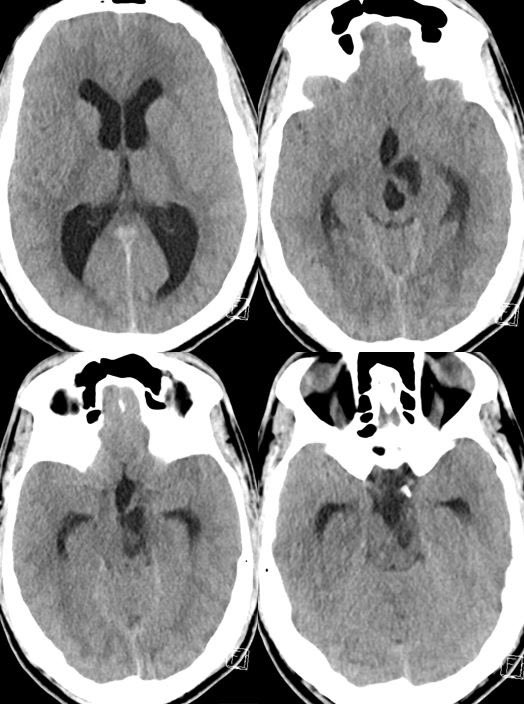

What is the most likely diagnosis in this 30 y/o M presenting with headaches? 🧠

🔷More images in 🧵